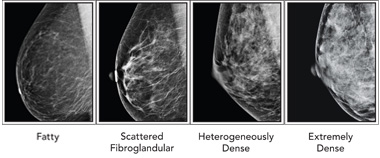

Although it is possible for some physicians to separate a very dense breast from a non-dense breast by a physical breast exam, the level of density is not possible to feel by touch. For that, physicians rely on mammography. Radiologists use a four category classification scheme when assessing the breast tissue on a mammogram called the Breast Imaging Reporting and Data System (BI-RADS).

The four classes, as indicated on the picture below, from left to right, are:

- Mostly fatty: The breasts are made up of mostly fat and contain little fibrous and glandular tissue. The mammogram would likely show anything that was abnormal.

- Scattered density: The breasts have quite a bit of fat, but there are a few areas of fibrous and glandular tissue.

- Consistent density: The breasts have many areas of fibrous and glandular tissue that are evenly distributed through the breasts. This can make it hard to see small masses in the breast.

- Extremely dense: The breasts have a lot of fibrous and glandular tissue. This may make it hard to see a cancer on a mammogram because the cancer can blend in with the normal tissue. (1)

In the above picture of the BI-RADS classification, the difference between dense and non-dense breasts seems clear. Technically, the last two of the four categories would fall under the umbrella category of "dense breasts." However, a recent study published in the Annals of Internal Medicine, through the NIH / National Cancer Institute, suggests that the classification of breasts as dense actually varies tremendously between physicians.